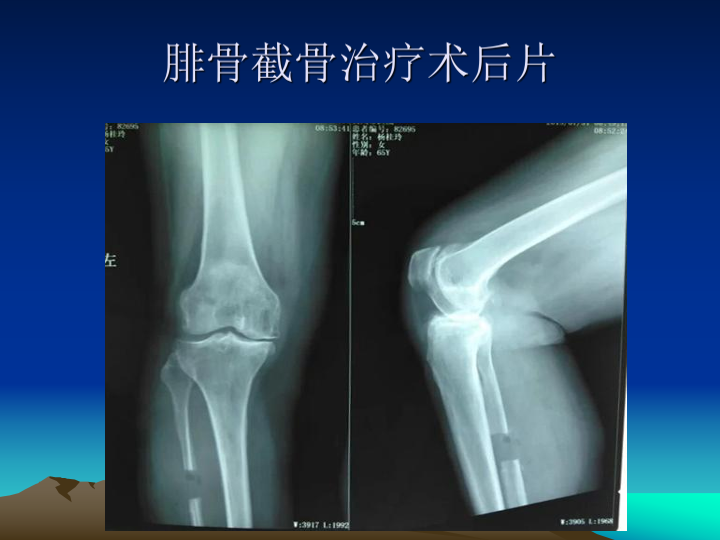

膝关节骨性关节炎阶梯治疗